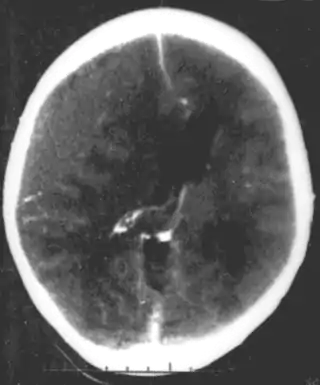

Las infecciones sistémicas pueden tener consecuencias en el desarrollo neurológico, cuando ocurren en la infancia y niñez de los seres humanos, pero no serían llamadas un trastorno primario del desarrollo neurológico per se, como por ejemplo, las infecciones por VIH de la cabeza y el cerebro, como los abscesos cerebrales, la meningitis o la encefalitis tienen un alto riesgo de causar problemas en el desarrollo neurológico y eventualmente un trastorno. Por ejemplo, el sarampión puede progresar a panencefalitis esclerosante subaguda.

Varias enfermedades infecciosas pueden transmitirse de forma congénita (antes o después del nacimiento) y pueden causar graves problemas de desarrollo neurológico, como por ejemplo los virus HSV, CMV, rubéola (síndrome de rubéola congénita), el virus Zika o bacterias como el Treponema pallidum en la sífilis congénita, que pueden progresar a la neurosífilis si no reciben tratamiento. Protozoos como Plasmodium o Toxoplasma que puede causar toxoplasmosis congénita con múltiples quistes en el cerebro y otros órganos, llevando a una variedad de déficits neurológicos.

El trauma cerebral en humanos en desarrollo es una causa común (más de 400.000 lesiones por año sólo en los Estados Unidos, sin información clara de cuántas producen secuelas en el desarrollo) de síndromes del desarrollo neuroógico. Se puede subdividir en dos categorías principales, lesiones congénitas (incluyendo lesiones que resultan de un nacimiento prematuro sin complicaciones) y lesiones que ocurren en la infancia o niñez. Las causas comunes de lesiones congénitas son la asfixia (obstrucción de la tráquea), la hipoxia (falta de oxígeno en el cerebro) y el traumatismo mecánico del propio proceso del parto.